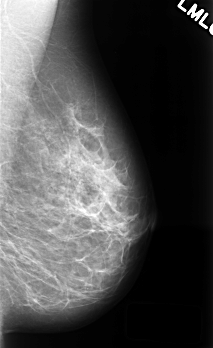

C_0415_1.LEFT_MLO

LEFT_MLO LINES 4520 PIXELS_PER_LINE 2768 BITS_PER_PIXEL 12 RESOLUTION 50 NON_OVERLAY